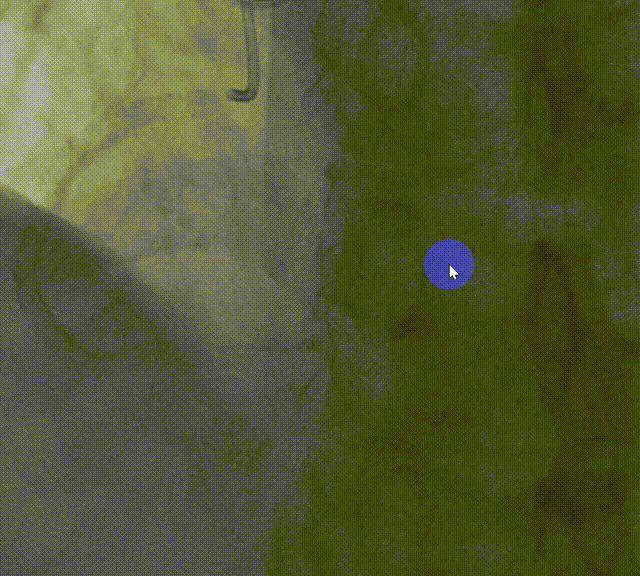

LM-LAD支架释放

LM-LAD支架释放后造影